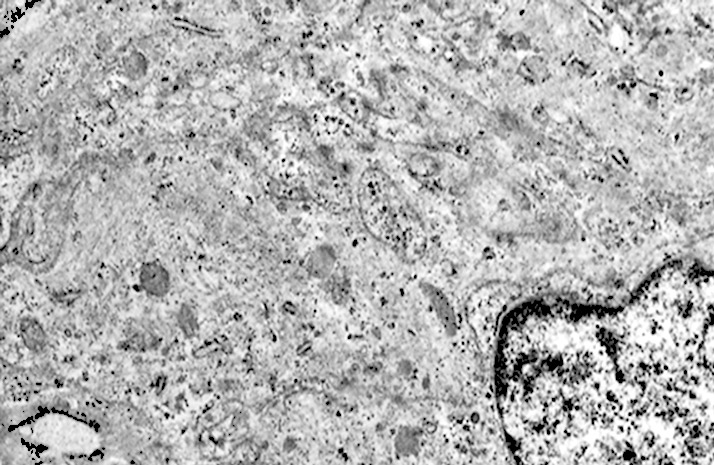

Al microscopio elettronico il citoplasma dei meningiomi meningoteliali appare ampio, ha un profilo irregolare, è fornito di prolungamenti citoplasmatici di varia lunghezza, ed è coeso alle cellule circostanti. Esso appare quasi sempre compatto anche se esibisce una densità del citosol molto variabile, fino ad immagini iperchiare, quasi trasparenti. E’ costantemente fornito di quote cospicue di organuli e di complessi proteici, e tutte queste substrutture sono distribuite in modo apparentemente uniforme nel citosol. Si evidenziano,infatti, numerosi quanto brevi segmenti di ergastoplasma rugoso, mitocondri piccoli, rotondeggianti e poveri di creste, reticolo endoplasmico liscio con cisterne ectasiche e apparentemente vuote, quote di ribosomi dispersi nel citosol, strutture di Golgi ben sviluppate, vescicole lisosomiali, numerosi microtubuli e quote variabili di filamenti intermedi variamente disposti in fascetti e orientati prevalentemente secondo l’asse maggiore della cellula. Il nucleo occupa una posizione centrale, ha un profilo irregolare, è voluminoso, è nucleolato ed ha un aspetto vescicoloso per la disposizione spaziale della cromatina lungo le fasce periferiche, a ridosso della membrana nucleare. Nel citoplasma di tali cellule si repertano in modo infrequente focolai non inerenti alla micro-architettura di tali elementi; essi sono distribuiti in modo apparentemente casuale e sono riconoscibili quali focolai di natura autofagica. Infatti, evidenziano una ultrastruttura formata da vescicole con gradi diversi di complessità e di ampiezza contenenti materiali diversi di natura biologica e organuli citoplasmatici. Su la base della complessità strutturale della loro morfologia si riconoscono focolai di microautofagia e di macro- autofagia in diversi stadi evolutivi.

Nel citosol si repertano vescicole di piccole dimensioni delimitate da una membrana di contorno a mono strato. Il loro lume è occupato da materiale amorfo e da corti filamenti distribuiti in modo disordinato.

Queste vescicole sono distribuite in modo irregolare, anzi casuale e si ritrovano ad essere isolate o riunite in piccoli aggregati formando un’immagine definita corpi multivescicolari.

Frequentemente questi focolai si ritrovano commisti ad altri aventi i caratteri della macroautofagia e sono in parte da questi mascherati. A parte questi particolari reperti,il citosol è occupato da numerosi mitocondri di piccole dimensioni e di forma rotondeggiante e di aspetto compatto,da ergastoplasma rugoso e da quote ben rappresentate di reticolo endoplasmico e di strutture lisosomiali.